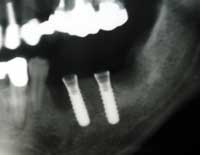

| 術前 | ソケットリフト手術 | 術後2年歯根周囲骨造成良好 |